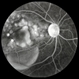

- metamorphopsia, pigment epithelial detachment (PED)

- Fundus camera

- 72-year-old man with VA loss and metamorphopsia of 2 months duration. PED found, testing done to rule out CNV.